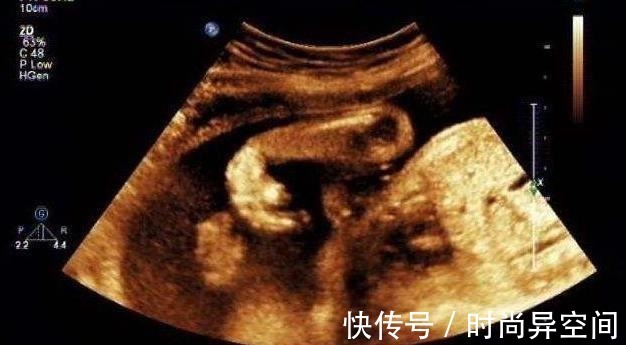

最近有网友在网上发布了一个奇怪的婴儿图片,图片上婴儿只有中一个眼睛,,当时下面评论声音一大片,问怎么样导致一个出生的婴儿长成这样,是污染,还是辐射。更多人治问婴儿妈妈为什么不产检,怎么没发现,这样的都让他来到人世间。

当然也和孕妇又没去产检有关系,所以导致这样一个结果,医生后来也说是由于辐射导致染色体异变造成的,因为婴儿一出生就查出患有罕见的染色体异常症,所以出生时只有一只眼睛,大脑里面也只有一个单一的半球,所以被称为独眼婴儿。

在当时医院出生的时候可是惊到了很多人,尤其是接产医生,因为当时是顺产,又是头先出来,当看到这样一个头出来时魂都没了,还好是一个经验丰富的医生,看的各种事情也多,家人看到时也哎生叹气的,都说造了什么孽。网友们对此事情怎么看,欢迎留言评论。事情已被凤凰网证实,图片来自网络。